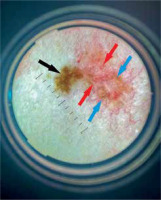

Dermoscopic picture of a collision of melanocytic naevus (left side; black arrow – regular, reticular pattern) and superficial BCC (right side; arborising vessels – red arrows, blue-grey ovoid nests – blue arrows)

Dermoscopy is commonly used to diagnose BCC. A pigmented reticular pattern is characteristic for melanocytic lesions such as naevi or solar lentigos. It is believed to be a negative diagnostic feature for pigmented BCC [13]. Nevertheless, it may rarely be observed in BCC lesions. Gulia et al. [14] published a study presenting 412 cases of BCC. Within 14 out of 412 (3.4%) lesions a typical pigment network was observed. In 9 tumours it was a result of collision with naevus, solar lentigo or actinic keratosis [14]. Such a collision (naevus and BCC) occurred also in one of analysed patients (Case 2).